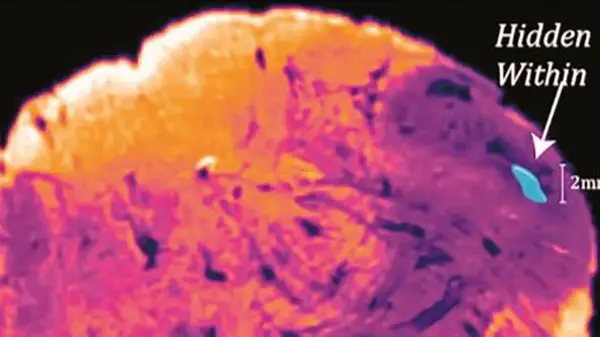

گفته شده این منطقه جدید از مغز احتمالا ارتباطی به بیماریهای عصبی و پارکینسون داشته باشد. بهگزارش نیواطلس، پروفسور جورج پاکسیونس که هماکنون در مرکز تحقیقات علوم عصبی استرالیا فعالیت میکند، منطقه جدیدی از مغز انسان را کشف کرده است. این منطقه تازه کشف شده

Endorestiform Nucleus نامیده شده است. دکتر پاکسیونس گفته، از ۳۰سال قبل احتمال میداد این بخش پنهان وجود داشته باشد اما فناوریهای نوین تصویربرداری امروزی منجر به کشف این منطقه شده است. هنوز عملکرد Endorestiform Nucleus مشخص نیست. قسمت مذکور نزدیک نقطه اتصال مغز و نخاع قرار دارد. در این منطقه اطلاعات حسی و حرکتی ترکیب میشوند تا تعادل و موقعیت بدن را بهبود بخشند. بهنظر میرسد این بخش فقط در انسانها وجود دارد. پاکسیونس در اینباره میگوید: این منطقه بسیار حساس است زیرا در میمونهای رزوس و حیوانات دیگری که مطالعه کردهایم، وجود نداشتهاست.اخبار 24 ساعت گذشته رکنا را از دست ندهید